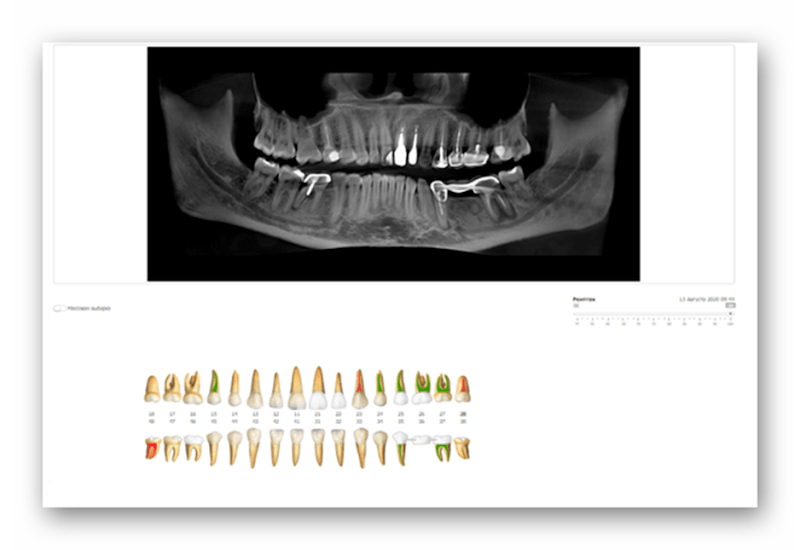

Diagnosis

Before dental treatment, a complete examination of the oral cavity must be performed. For this purpose, a CT scan or an orthopantomogram is indicated.

Based on X-rays and visual examination, the following issues are determined:

- hopeless teeth – they will have to be extracted;

- conditionally preserved – you can try to treat them, but if the result is negative, they will be pulled out;

- teeth requiring treatment – they can definitely be preserved;

- healthy teeth – they need no treatment.